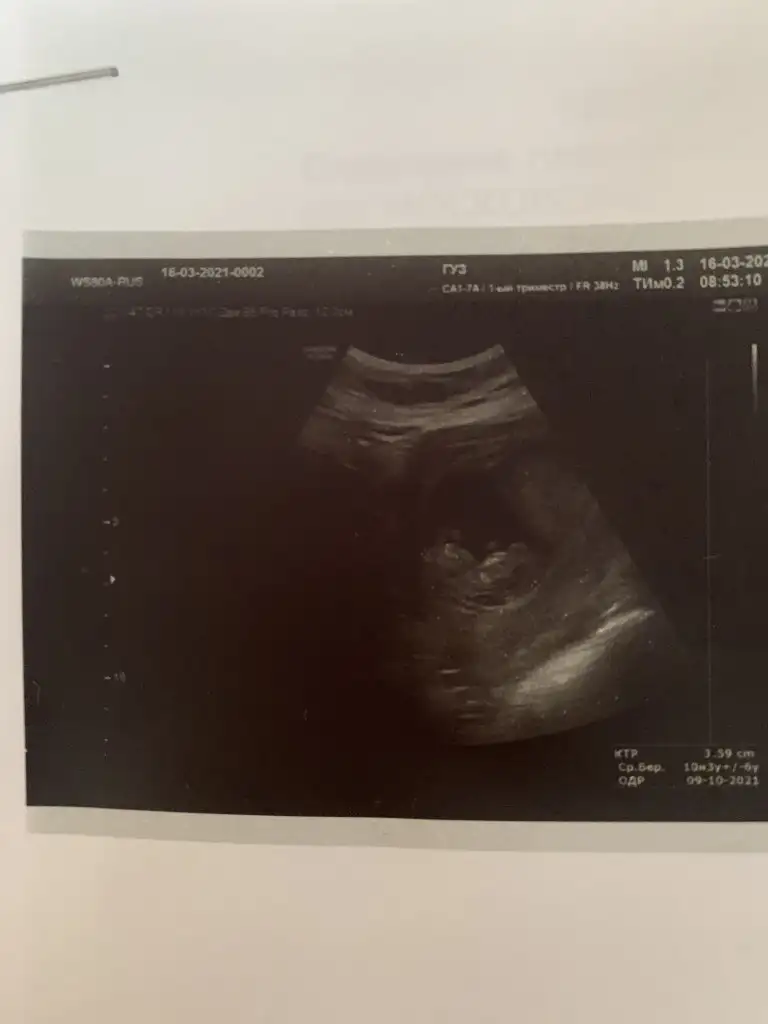

Merhaba rica ediyorum bunada bakın. Vajinal ve burada 10+3

Selisay ikinci gidişim Dr a ilki minik yuvarlak keseydi bugünkü bu nabzı 124 çıktı

Eklentiler

• IMG_20210331_155424.webp

IMG_20210331_155424.webp

25,3 KB · Görüntüleme: 1.170